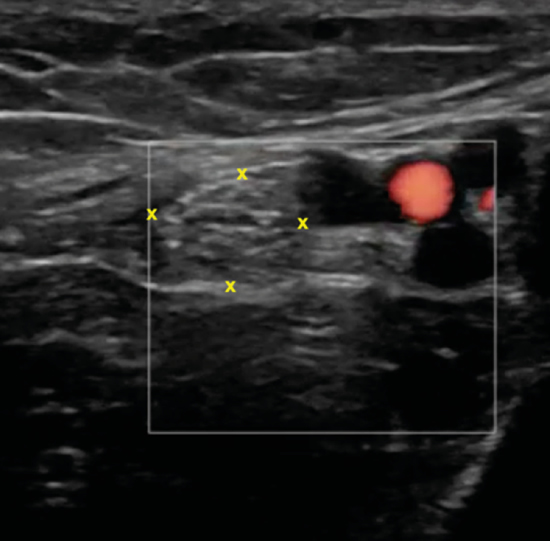

Se sitúa la sonda en el plano transverso (Figura 8) para localizar el nervio tibial en eje corto, y apreciar en un discreto desplazamiento distal como la rama calcánea se irá separando y distanciando en busca del aspecto posteromedial del calcáneo (Figura 9).

Figura 9. En esta imagen en eje corto, la rama calcánea (flechas) una vez que ha atravesado las láminas de la fascia crural (*) y se ha ido separando del nervio tibial (NT) que se encuentra debajo de los vasos (A, V), y sobre el tendón flexor largo del primer dedo (FLD) y el astrágalo (AST).